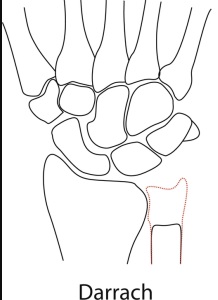

In uw pols is in het gewricht tussen het spaakbeen en ellepijp (het DRUJ) artrose ontstaan. De oorzaken hiervoor zijn: niet anatomisch geheelde fracturen van de pols, (onbehandelde) bandletsels van de pols, instabiliteit, kraakbeenslijtage, reuma of groeiafwijkingen (Madelung) van de pols.